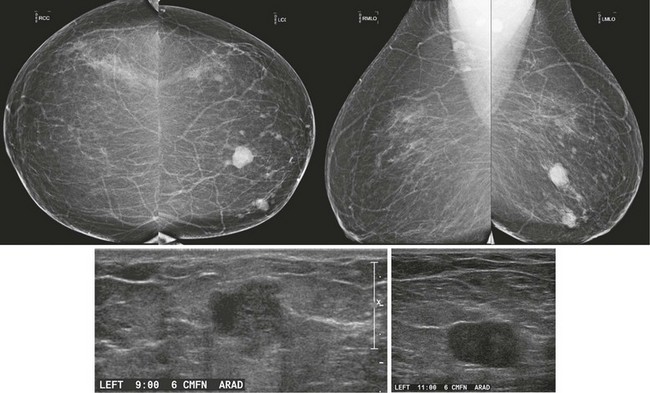

CASE 8-8. There are at least three new bilateral isodense masses with circumscribed margins (arrows). There were no masses on prior mammograms; therefore, diagnostic views and US were performed. CC spot compression views show circumscribed margins. US reveals bilateral oval solid masses. Core biopsy of masses in the 12 o’clock position of the right breast and the 10 o’clock position of the left breast both revealed previously unsuspected extranodal marginal zone B-cell lymphoma.